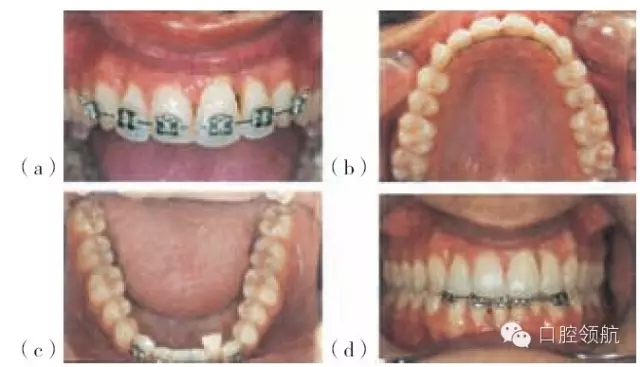

圖29.7 (a,b)圖29.4患者牙周治療之后的圖片,該患者不喜歡左下中切牙的位置及外觀,并希望盡可能保留該牙齒(有唇塌陷和局限性退縮)

圖29.8 圖29.7患者正畸治療的過(guò)程:(a)上頜固定矯治器。(b)上頜腭側(cè)保持器。(c)下頜固定矯治器。(d)排齊(永久保持)的上頜前牙及下頜固定矯治器。

左上中切牙經(jīng)正畸治療后更加美觀